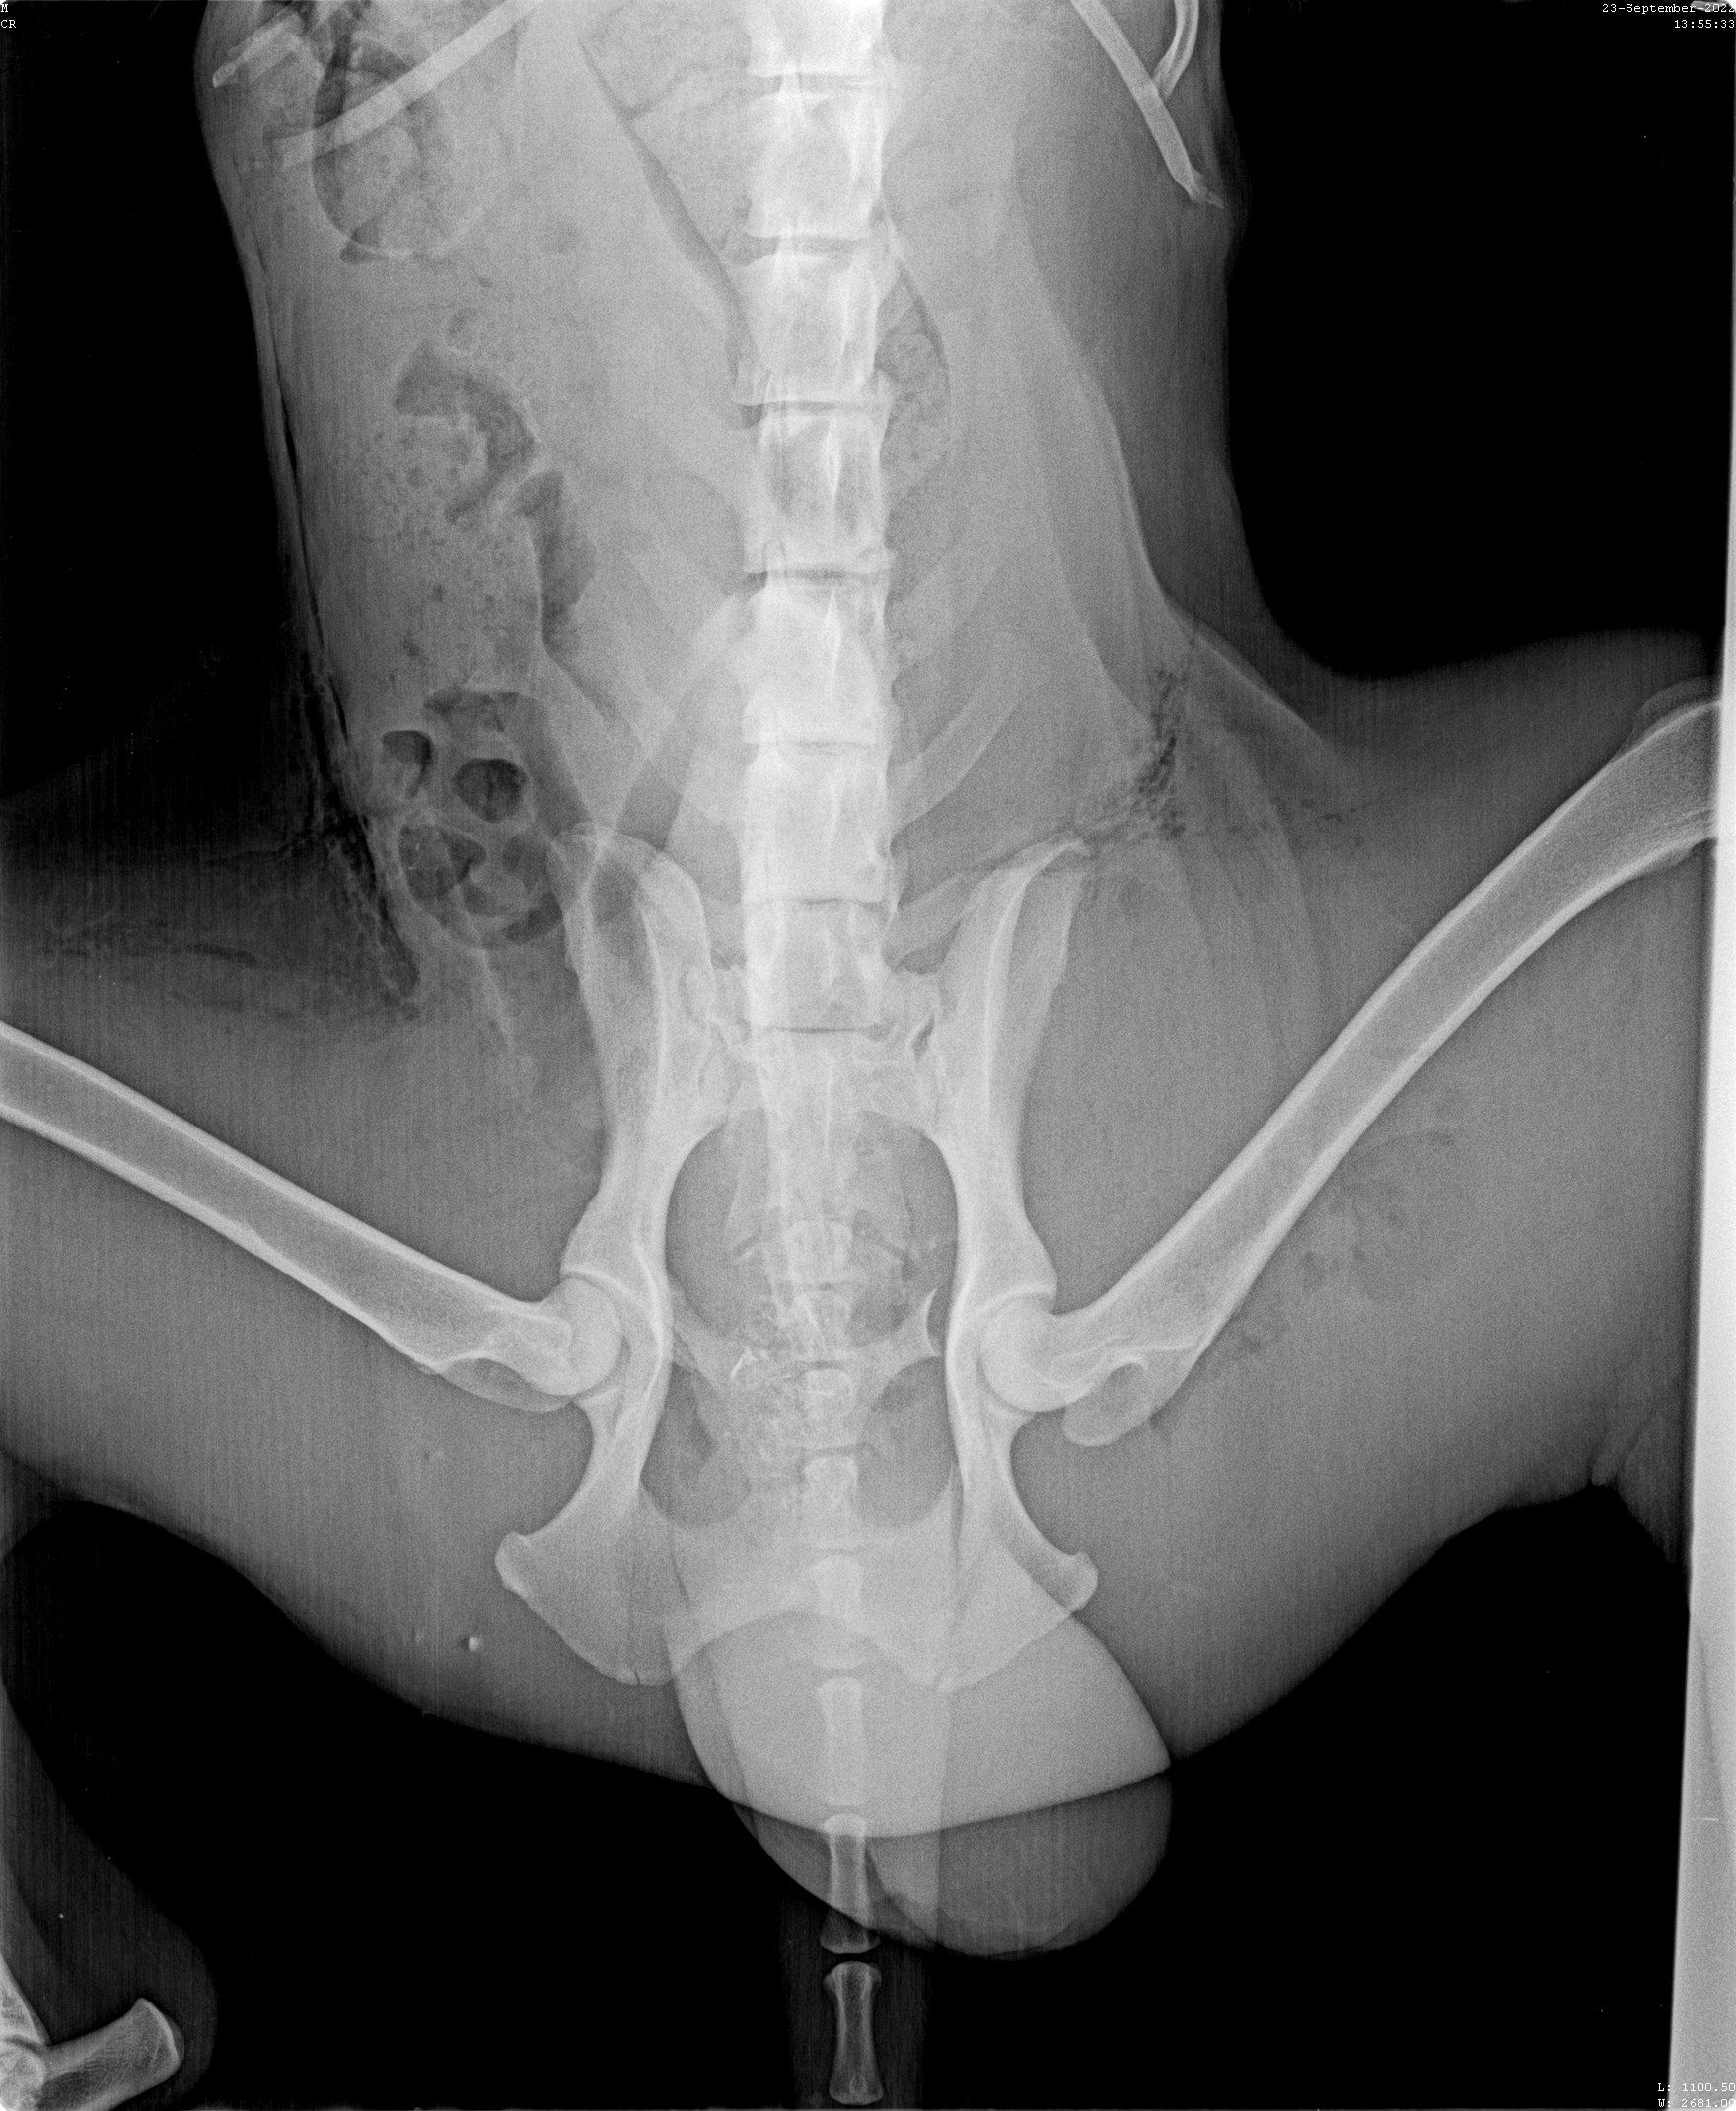

Oktober 2022

Update zu Kilian

Kilian war angefahren an der Autobahn aufgefunden worden. In der Klinik, wo er drei Tage verbleiben musste, da die offenen Wunden gereinigt werden mussten und sein linkes Bein Sorgen bereitete. Die Lähmungen sind wohl zurückzuführen auf den gebrochenen dritten Lendenwirbel, der niedriger lag als die Wirbelsäule. Dies bedeutet Ruhe halten, eine OP kann folgen müssen. Die offenen Wunden am Hinterleib sowie am Hodensack waren äußerst schmerzhaft, so wird er nun weiter mit Antibiotika und mit Fieber senkenden Mitteln behandelt. Die Kosten belasten unser Budget schon sehr, aber Hilfe hat für uns Vorrang.

Für jede Spende für Kilian sind wir dankbar! Jeder Cent kommt an! 🍀

Kilian - Opfer eines Rücksichtslosen

Angefahren und liegen gelassen worden ist dieser Rüde von Aliki auf dem Weg nach Kavala am Straßenrand gefunden worden. Zusammen mit Richarda ist Kilian ins Krankenhaus gebracht worden wo zuerst einmal die Wunden gereinigt wurden, mehrere offene Wunden mussten genäht werden, ein Beinbruch ist offensichtlich, doch das Röntgengerät war kaputt, so dass hier erst später Genaueres gesagt werden kann. Dieser hübsche Settermix litt unendlich, hoffen wir, dass unsere Hilfe ausreichen wird.

Wer mag sich an diesen Kosten beteiligen und Pate Kilians werden?

Update zu Kilian🐕

Dieser Setter-Mix, der den treffenden Namen Kilian erhalten hat - er braucht wirklich einen Schutzengel- ist direkt zum Arzt gebracht worden, der zuerst einmal sämtliche offenen Wunden desinfiziert hat und damit den ersten Heilprozess angestoßen hat. Nun war das Röntgen-Gerät defekt, weshalb er nun erneut zu einer Klinik gebracht werden musste, um seine Hüfte zu röntgen, da bei dem Autounfall vermutlich nicht nur diese fürchterlichen äußeren Wunden zurückblieben. Kilian verhält sich sehr tapfer, hoffen wir, dass die Hilfe, die er in Griechenland erhält, auch von Deutschland aus weiter unterstützt wird. 💕Wer mit einer (einmaligen oder monatlichen) Spende Pate dieses Unfallopfers werden möchte, kann dies über folgenden Link! 💙